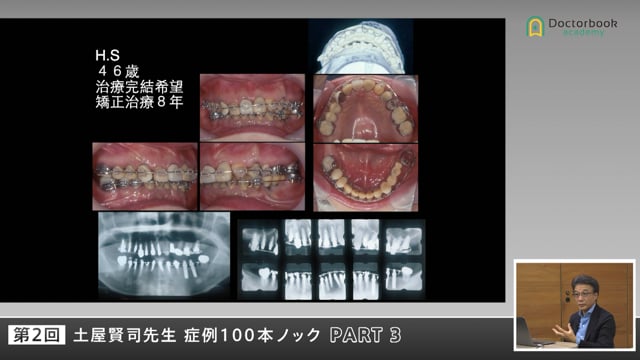

今回はCase 4です。

まずはパノラマ写真から読み取れる、多くの情報を全員でディスカッションしています。

バーティカルストップはどうなっているのか。

大臼歯部における展開角はどうでしょうか。

アンテリアガイドの重要性を教えてくれる症例となっています。

12年後のパノラマ写真を提示してくれています。